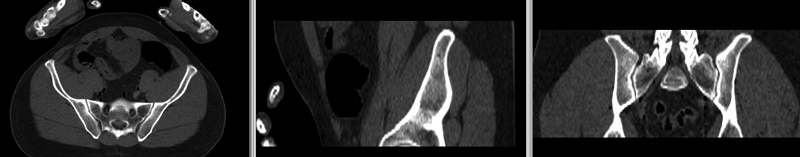

File:RegLib C44 registered withMask.gif

RegLib_C44_registered_withMask.gif (800 × 157 pixels, file size: 154 KB, MIME type: image/gif, looped, 2 frames, 1.0 s)